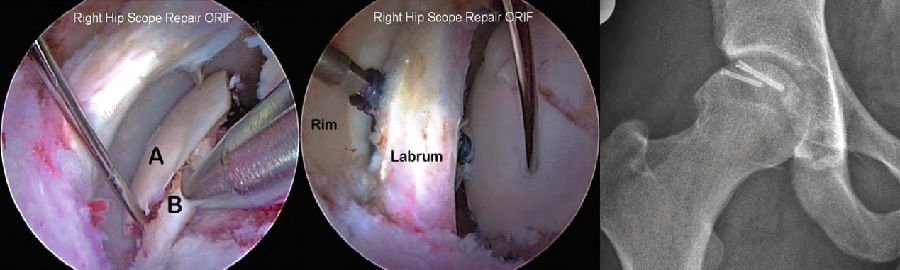

1. 髋臼盂唇损伤

髋臼盂唇损伤是导致髋关节疼痛的最常见原因之一。导致骸臼盂唇损伤的因素很多,包括运动损伤、创伤、年龄、髋关节结构及发育异常如髋臼发育不良等、炎性疾患等,以运动损伤和训练伤最为常见。盂唇损伤最常见于前上方,后方损伤相对少见。从撕裂累计的区域看,盂唇和软骨结合部位最易发生损伤。依据病史、体征、有效的辅助检查或关节镜检查,诊断髋臼盂唇损伤并不困难。通常从事剧烈运动的年轻患者运动后出现腹股沟区疼痛时,可考虑盂唇损伤。非手术治疗可以缓解症状,但不能去除病因,经3-6个月保守治疗无效建议行手术治疗。切开手术的优点是视野好,可在直视下进行修复,多数患者能获得满意的临床结果,但手术创伤大,术后康复时间长。髋关节镜手术创伤小,可直达髋关节中央和外周间室,不仅能处理损伤的盂唇,还可以对髋臼和股骨头颈区骨性异常进行评价和处理。目前关节镜手术盂唇损伤修复是主流方法,主要包括盂唇修整、盂唇修补和盂唇重建。

2. 髋关节撞击症

髋关节撞击征(femoroacetabular impingement, FAI)是引起中青年,特别是运动量较大者髋关节疼痛的主要原因,也是引起早期骨关节炎的重要因素。按受累解剖部位形态学改变,FAI 可分为:(1)凸轮型撞击(cam impingement);(2)钳夹型撞击(pincer impingement);(3)凸轮钳夹混合型撞击(mixed type)。该病好发于喜欢运动的青壮年,患者常有不明原因的髋关节慢性疼痛,以腹股沟区最为多见,也可出现股骨后侧和外侧疼痛,同时伴有髋关节活动受限,以屈曲内旋受限最为显著。通过髋部X片(包括骨盆正位X线片、髋关节穿桌侧位、蛙式侧位X线片、屈髋侧位片或假斜位片)、MRI和CT检查一般不难诊断。一般经休息、限制髋关节运动、服用非甾体抗炎药以及封闭治疗等保守治疗无效可考虑手术治疗。治疗方面,早期主要是通过股骨头脱位技术进行开放手术治疗,目前的主流是通过髋关节镜微创技术进行治疗,包括镜下清理凸轮畸形,恢复股骨头颈区的自然弧度;清除髋臼边缘的骨赘和适当磨除髋臼周围影响髋关节活动的骨质,以减少髋臼前方的过度覆盖,最后把髋臼盂唇剩余部分缝合固定在骨面或髋臼缘上。